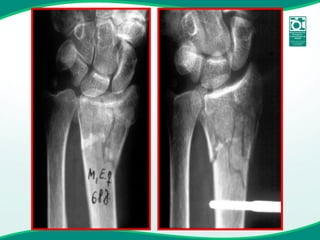

• #35 Here’s a nasty comminuted, articular fracture of the distal radius treated by bridging the joint with the fixator.

• #36 Here’s the healed result.

• #37 This shows the use of the Fragment Fixation System implants as a supplementary technique to restore the articular surface of the radius and reattach the ulnar styloid.

• #38 Here is the excellent functional result.